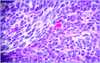

A 55 year old woman with a 30-year history of systemic lupus expires from an MI due to CAD. She had developed multiple manifestations of the disease (cutaneous, pulmonary “shrinking lung”). Additionally, according to her children her mental “sharpness” had declined in recent years. Based on the histology of her brain, what may she have developed?

Vasculitis of cerebral blood vessel:

Secondary vasculitis of the CNS (more common) can be part of a variety of systemic illnesses including generalized

autoimmune disease such as:

- SLE

- Sjogren’s syndrome

a variety of systemic vasculitides such as:

- Wegener’s Granulomatosis

- Polyarteritis nodosa

Primary CNS vasculitis (primary angiitis of CNS):

- No other disease or condition causing vessel damage

- Often granulomatous (below)